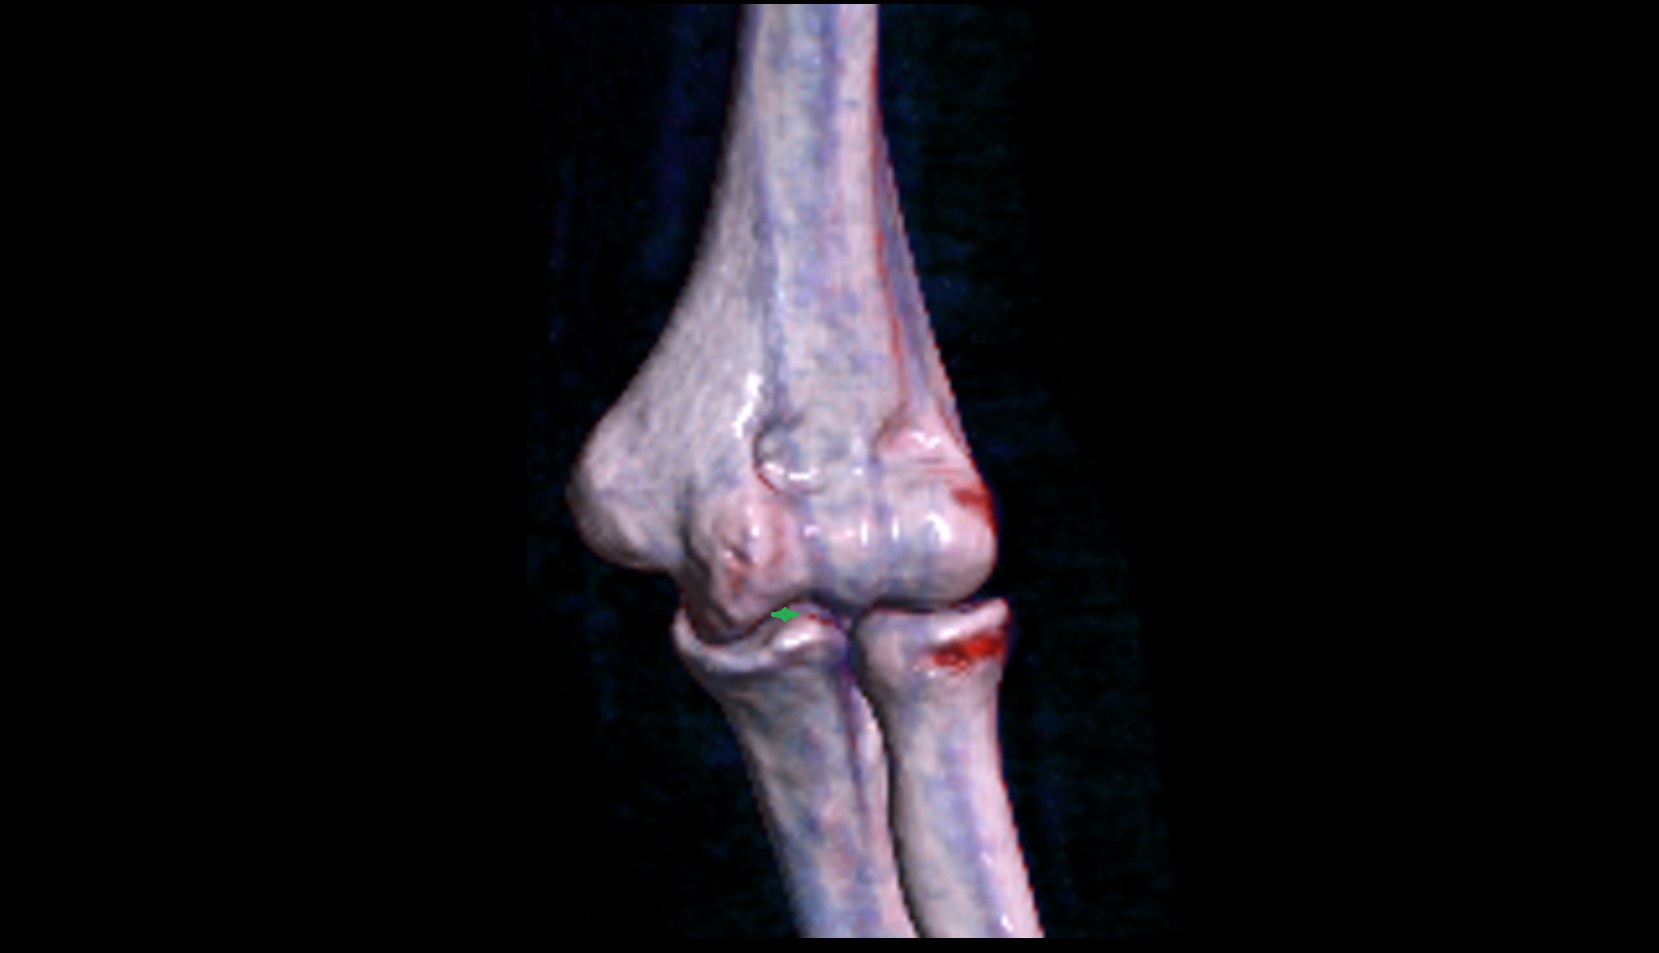

- Elbow joint